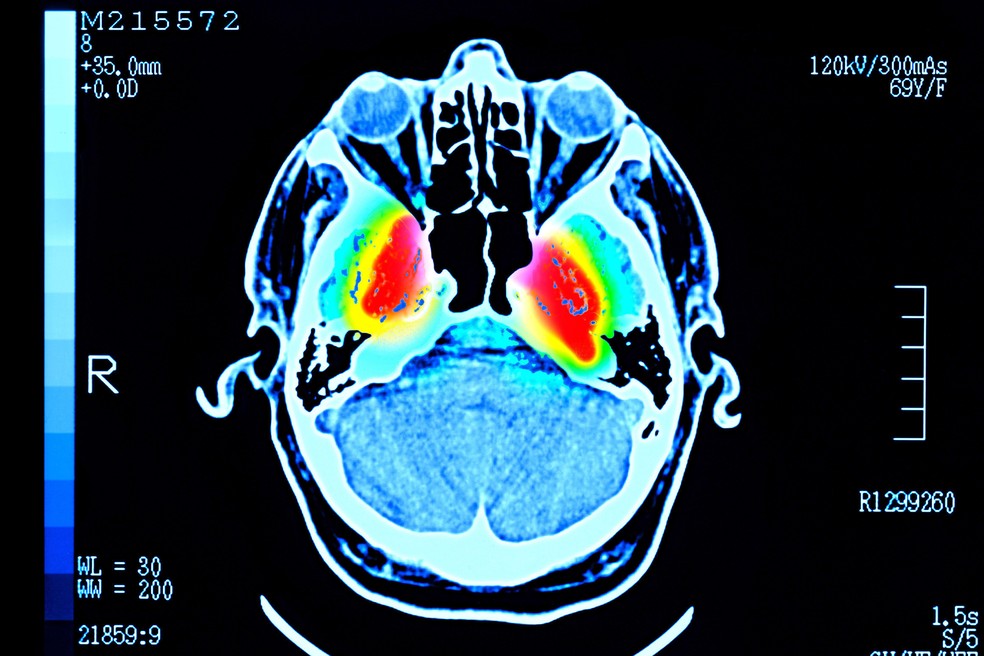

O cérebro passa por cinco fases distintas ao longo da vida, com momentos de virada aos 9, 32, 66 e 83 anos, apontam cientistas.

Cerca de 4.000 pessoas de até 90 anos fizeram exames que mostraram as conexões entre suas células cerebrais.

Esses padrões só agora aparecem devido ao volume de exames cerebrais reunidos no estudo, publicado na revista científica Nature Communications.